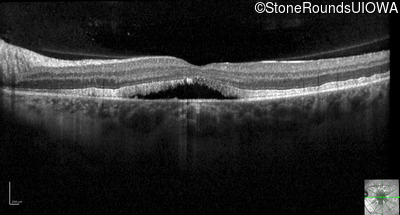

Optical Coherence Tomography - Right - 20/25

Exemplar / OCT Stack